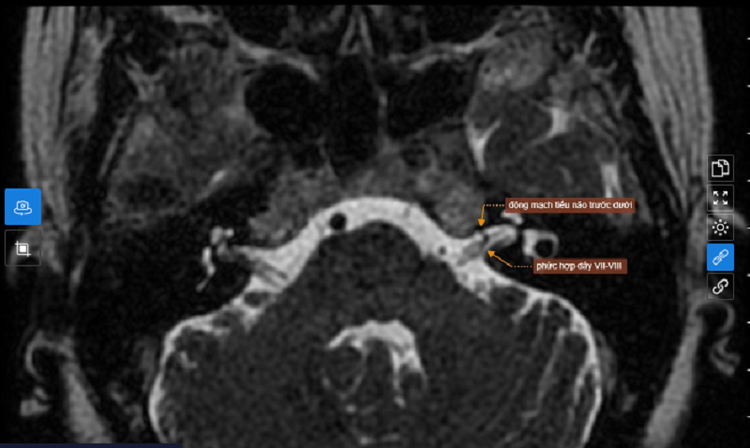

| Chụp MRI sọ não cho hình ảnh thoái hóa myelin chất trắng dưới vỏ bán cầu đại não và quanh não thất bên hai bên. Bệnh BVCC |

Về chẩn đoán hình ảnh, chụp MRI sọ não có hình ảnh thoái hóa myelin chất trắng dưới vỏ bán cầu đại não và quanh não thất bên hai bên.